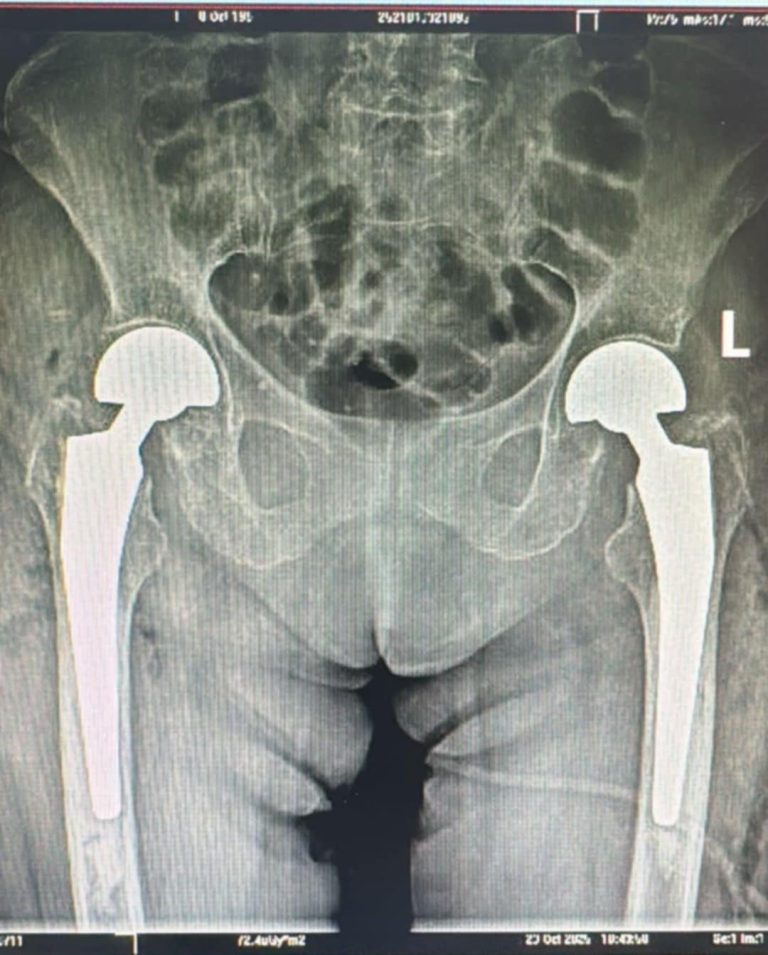

FOTO: Intervenție în premieră la Spitalul Județean Sibiu. Artroplastie parțială de șold bilateral

ULTIMA ORĂ/FOTO: Intervenție în premieră la Spitalul Clinic Județean Sibiu